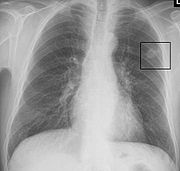

سرطان الرئة

| سرطان الرئة | ||

| معدل الانتشار | 3.3 مليون (2015)[7] | |

| معدل البقاء 5 سنوات | 17.4% (الولايات المتحدة)[8] | |

| حالات الوفاة | 1.7 مليون (2015)[6] | |

| عوامل الخطورة | تدخين السجائر (يرتبط بنسبة 85- 90% من جميع الحالات)؛ التعرض في مكان العمل لمواد معينة (منها الأسبست asbestos وبعض المواد الكيميائية العضوية)؛ التعرض للإشعاع؛ التعرض لغاز الرادون (لا سيما عند المدخنين)؛ وجود دخان التبغ في البيئة. | |

| العلامات المنذرة | سعال مستمر؛ قشع مختلط بدم؛ تنفس وزيزي؛ ألم كتفي أو صدري؛ انتفاخ (تورم) الوجه أو الرقبة؛ التهاب الرئة أو التهاب القصبات المتكرر. | |

| الكشف والتشخيص | صورة صدر شعاعية، تحليل الخلايا التي في القشع، فحص المسالك القصبية بالمنظار الليفي الضوئي. | |

| العلاج | إن سرطانات الرئة نوعان أساسيان: صغير الخلايا small cell وغير صغير الخلايا. ويعالج سرطان الرئة صغير الخلايا الذي ينتشر بسرعة، بالعلاج الكيميائي وحده أو بالمشاركة مع المعالجة الشعاعية بدلا من الجراحة. يوجَّه الإشعاع نحو الصدر، وفي بعض الحالات نحو الدماغ لقتل النقائل الورمية. وبالنسبة لسرطانات الخلايا (الرئوية) غير الصغيرة الموضّعة، فباستطاعة الجراحين إزالة الجزء المصاب من الرئة على الرغم من أن الانتكاسات شائعة؛ أما بالنسبة للحالات المتقدمة فيمكن استخدام المعالجة الشعاعية أو المعالجة الكيميائية أو المعالجة بالليزر أو بالجمع بين بعض هذه المعالجات عوضا عن المعالجة الجراحية.

| |

| ملاحظات | * انخفض معدل حدوث هذا المرض عند الرجال منذ الثمانينات ولكنه ما زال يرتفع عند النساء.